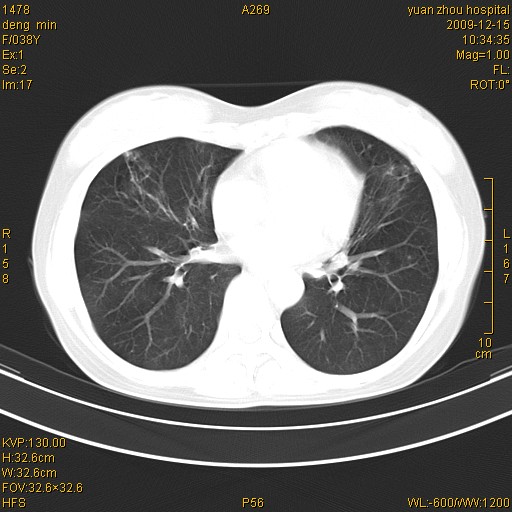

标题: CT23919:F38Y 咳嗽月余 [打印本页]

标题: CT23919:F38Y 咳嗽月余

支气管扩张。典型。

右肺中下叶、左肺上叶舌段及左肺下叶支气管扩张合并感染。